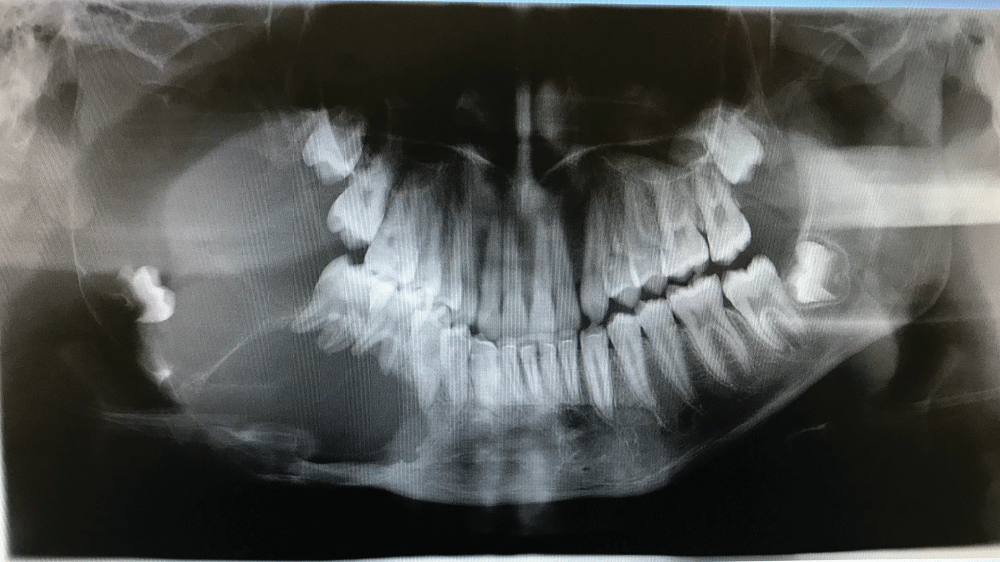

Figure 1: Pre-operative OPG showing the extent of the ameloblastoma involving the entire right hemi-mandible, and including the mandibular condyle and coronoid process. View Figure 1

A 17-year-old male patient presented with right-sided facial asymmetry, and a large bony mass that was painless could be palpated in the lower jaw. The teeth of the involved hemi-mandible were mobile, and there was paraesthesia of the distribution of the lower right inferior alveolar nerve. The patient presented with no systemic compromise, and was otherwise well. A benign neoplasm (Ameloblastoma) was suspected and confirmed via incisional biopsy of the right hemi-mandible (Figure 1). A right-sided hemi-mandibulectomy with disarticulation, was subsequently performed via an intra-oral and pre-auricular approach. A preformed reconstruction plate with add-on condyle (DePuy Synthes CMF, West Chester, PA) was used together with an alloplastic Temporomandibular joint (TMJ) fossa (Zimmer Biomet CMF, Jacksonville, FL) (Figure 2). An allogenic demineralised humerus (Bone SA, Bramley, Johannesburg, South Africa) was used as a conduit for a compacted autogenous PCCB graft, harvested from the anterior iliac crest. This bone conduit was then secured to the reconstruction plate (Figure 3) and the intra-oral access closed in two layers. Maxillomandibular fixation (MMF) was applied (released after 4 weeks), and a nasogastric feeding tube (NGT) inserted. The Patient was fed for seven days via NGT and was kept on antibiotic prophylaxis and analgesia for that duration, and then discharged from hospital. Follow-up occurred at regular intervals for 18 months after the surgery (Figure 4).